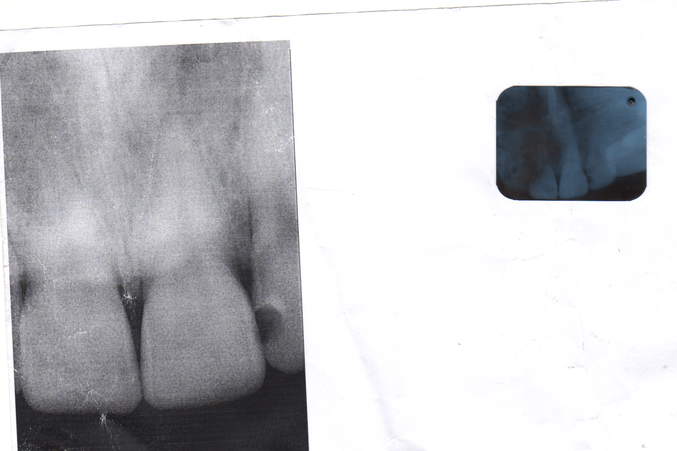

Здравствуйте!Месяц назад меня ударил мой ребенок лбом по губе так сильно,что задел зуб верхний центральный.С зуба пошла кровь,боль была очень сильная.Потом около недели я не ела на зуб этот,чувствителность оставалась,боли как таковой не было.Через неделю сделала ренген,стоматолог ничего не увидел.Сейчас прошло 35 дней,чувствительность присутствует,боли нет.Вот сегодня сделал ренген врач опять,видно воспаление.Наощупь тоже чувствуется немного ,что десна этого зуба приподнята,не так чтоб сильно,на глаз незаметно. Сказал пить антибиотики,и выписал еще раствор полоскать от воспаления.Больше ничего! Я очень переживаю, не хочется остаться без переднего зуба в 26 лет...

Здравствуйте!Вот отсканировала.Первый снимок,который побольше,был сделан через 5 дней после удара.Второй-через 35 дней. Зуб, получается, центральный левый,тот который через один от зуба с кариесом. Спасибо за внимание!